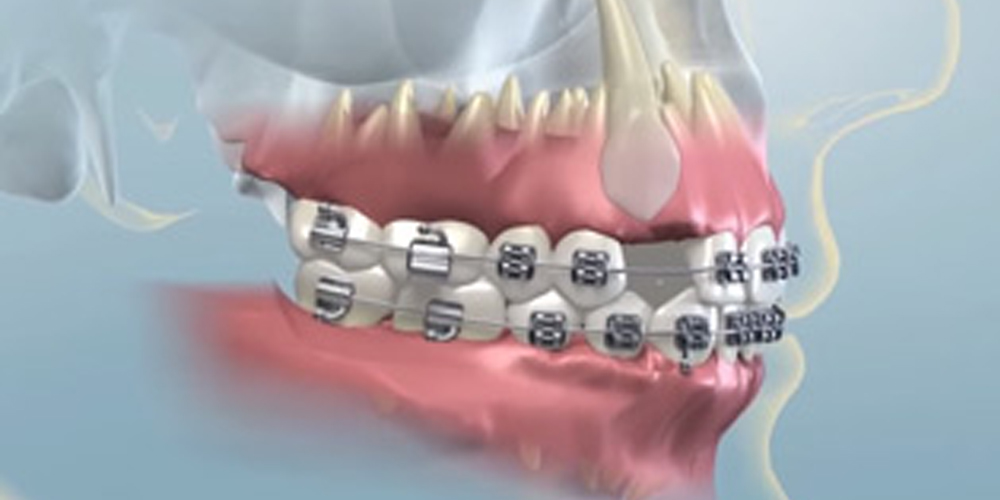

Even if we clear space for the canines, they will likely need to be “pulled down” into place with braces.

The surgery to expose impacted canines takes just about 45 minutes. It is a comfortable procedure that is done under local anesthesia in most instances. Occasionaly general anesthesia may be needed . Mild swelling and soreness may occur for several days following, and can be managed adequately with over the counter pain medicines. During the surgery, the crown of the tooth is uncovered. Depending on the severity of impaction, we may attach a bracket and gold chain to the tooth to “pull” it into place, or we may simply apply a dressing and let it find its own way. It is important to maintain good dental hygiene as part of your home care practice.